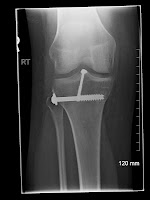

En dan was het weekend.. Tijd voor mij om voor de eerste keer naar de kinésiste te gaan hier.. En ik moet eerlijk zeggen, de weg ernaartoe is al een heuse training :-D Maar het gaat goed.. De kleine, simpele oefeningetjes zijn wel ontzettend vermoeiend..maar ik bijt door, zoals jullie het gewend zijn van mij :-) Ondertussen mag ik mijn been ook al tot 90° leren buigen.. Olé :-)